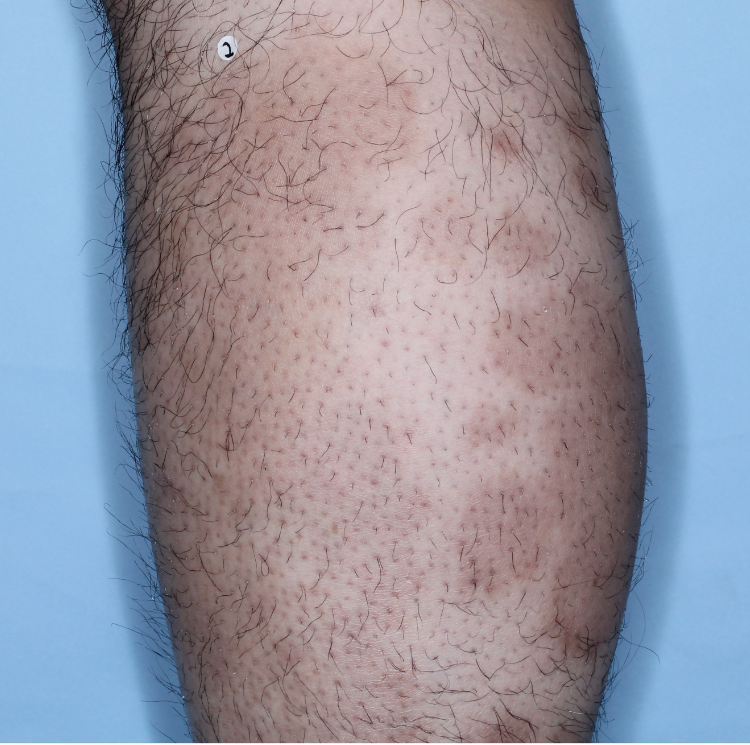

Patients saw clearer skin at Week 16 and Week 481,2

Week 0

PASI=20.6

Week 16

PASI=2.9

(86% PASI

improvement)

Week 48

PASI=1.10

(95% PASI

improvement)

Individual results may vary.

Images are Janssen-owned from blinded trial: NCT05272150.